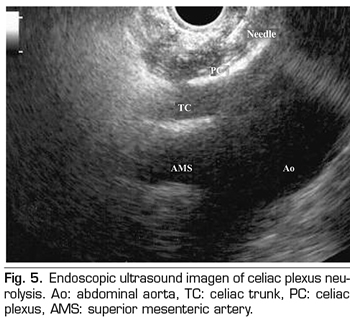

Figure 5